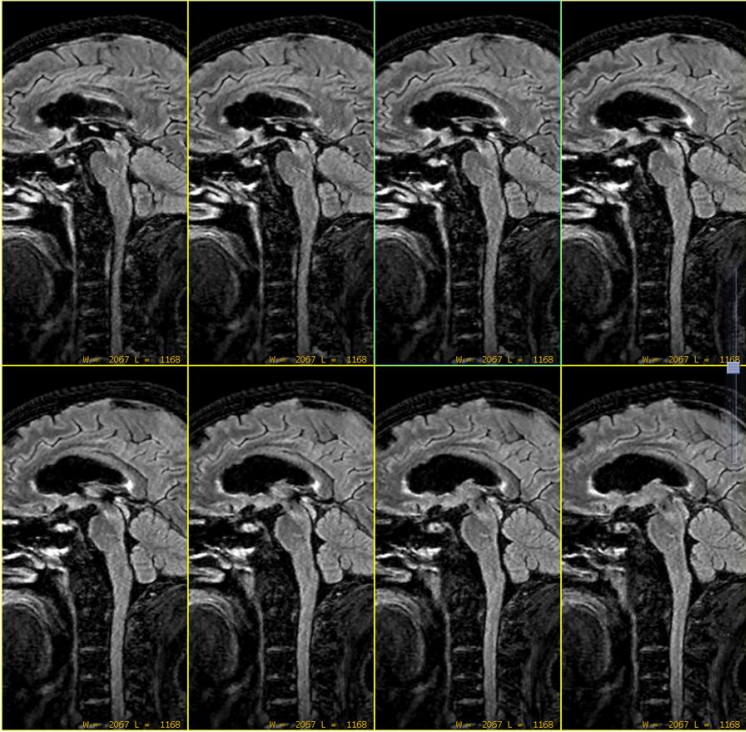

1分半快速TOF MRA两侧血管基本对称 扫描结束,放病人走? 但是患者突发失语症状,如果这么回去,临床如何治疗呢? 想到扫描更薄层图像看下,由于病人有些躁动需要快速扫描,于是扫描了快速薄层CUBE T2FLAIR,Voxel size = 1X1X1mm; 三维加速技术2X2X2,8倍加速,扫描时间2分半钟:

可见中脑位置似乎有异常稍高信号灶。但是患者开始出现运动。此时留给技术组老师的时间已经不多了。 然而,经过简单有效沟通后(扯着嗓子喊了一声:别动),扫描继续。 Sag DWI b=1000s/mm2,层厚3mm,0间隔扫描,扫描时间36秒: